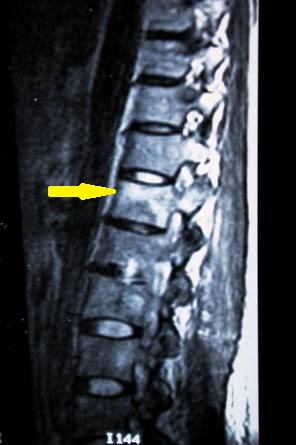

- Figura No 1a

- Figura No 1b

- Figura No 1c

- Figura No 1d

- Figura 1 Texto